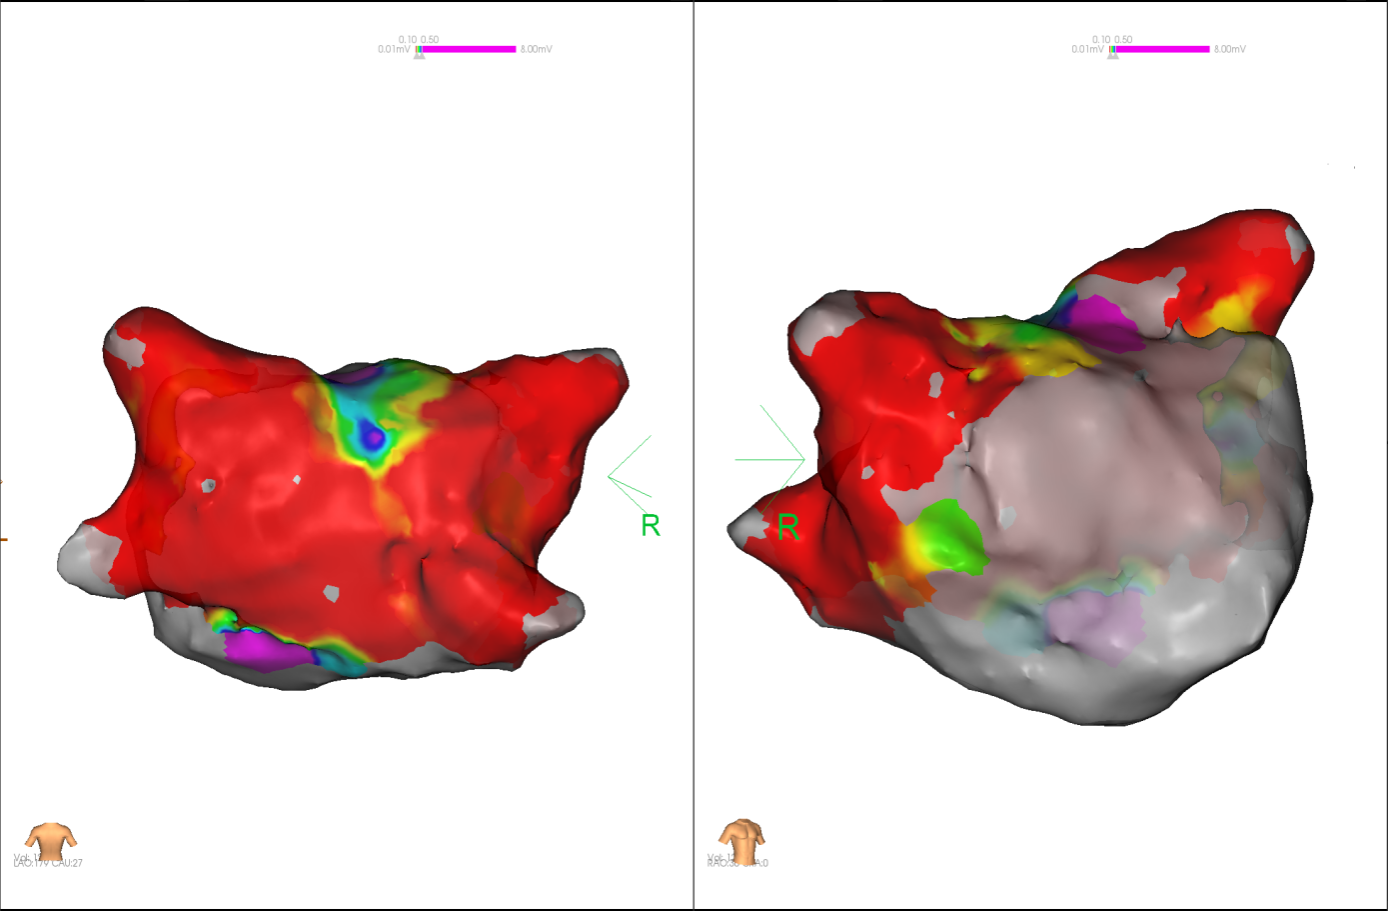

经充分术前评估及准备后,该患者手术在抗心衰药物持续静脉泵入、高流量吸氧支持下及麻醉、护理团队的通力配合下进行,由薛建颖、崔明亮主治医师具体实施。术中通过右侧股静脉送入心腔内超声至右心房,排除左房血栓后成功指导房间隔穿刺,沿可调弯鞘管送入锦江心脏脉冲电场消融导管至左房,构建左房三维解剖模型并行基质标测,标测显示左房基质差,分别行左侧、右侧肺静脉及后壁BOX消融。消融参数:1800v,400ms,400μs,共放电消融140次(消融右肺静脉时转复为窦性心律),验证双肺静脉均隔离。术后重新标测显示所有肺静脉均已急性阻滞,消融效果理想,肺静脉前庭损伤范围也达到了预期的标准,同时心腔内超声监测未见明显心包积液。手术仅用时30分钟,时间明显缩短,手术过程精准高效。术后患者恢复情况良好,维持窦性心律。

图3 PFA于右肺静脉后壁交叉消融时转为窦率,继续消融

图4 消融前后基质标测提示肺静脉消融效果明显